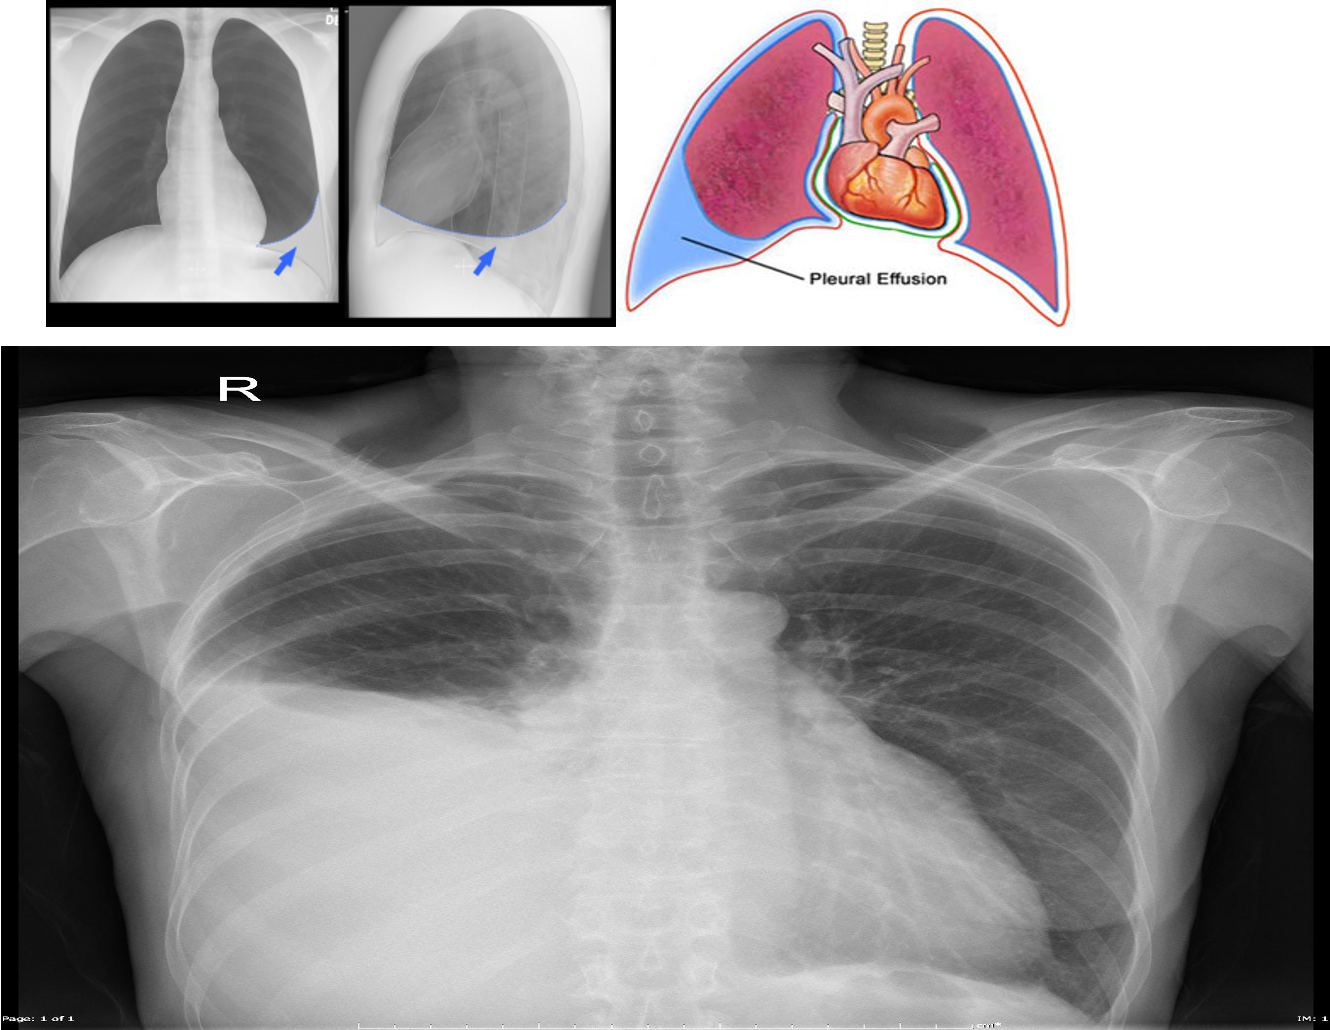

Imaging to confirm the diagnosis:

Chest X-ray: Lateral decubitus view (most sensitive): > 200 ml.

- Unilateral blunting of the costophrenic angle

- Homogeneous density with a meniscus-shaped margin (meniscus sign)

- Complete opacification of the lung (Large effusion) and Mediastinal shift and tracheal deviation.